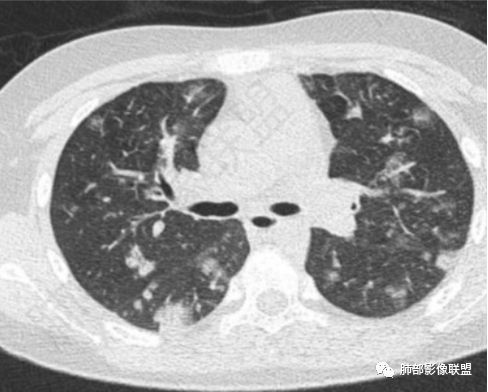

患者河里游泳,受伤,发热,血压低到休克,呼吸困难三凹征,血气提示呼吸性碱中毒合并代谢性酸中毒且代酸占上峰,肺部表现既无明显出血的磨玻璃影(不符合钩体导致出血的特征)又无多发影内空洞(这点不符合金葡菌),是真菌感染的影像,河水属污水,故肺部表现为:尖端赛多孢子肺炎(这个菌感染重,死亡率高)!

肺部影像联盟晨读病例如果是非流动河水、溺水,考虑尖端赛多孢子菌。助攻一例如下:

这是尖端赛多孢子菌 |

学习了,溺水,特别是污水,要想到尖端赛多孢子菌

从放射科来讲:尖端赛多孢子菌和SPE阴影分布特点,如气道、还是随机分布,影像是否有区别?理论上尖端赛多孢子菌应该是气道,而血播金葡是随机,可惜我掌握不好。